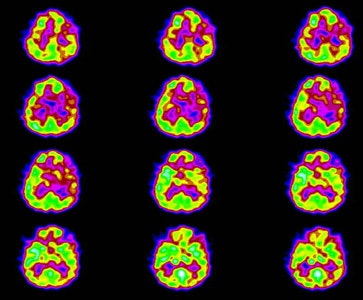

Patients with Lyme encephalopathy generally show a poor response to medications that would ordinarily be helpful and the patient's psychiatric findings can improve with antibiotic treatment alone [8]. Lyme encephalopathy most commonly produces a multifocal pattern of hypoperfusion affecting both the cortex and deep structures [6,8]. Significant perfusion abnormalities can be identified in up to 50% of affected patients [8]. Diffusely reduced cerebral cortical flow has also been described [7]. SPECT imaging can also be used to monitor response to therapy as areas of abnormal perfusion can reverse with treatment [6].

Neuro lyme: The patient below complained of intermittent right facial numbness, memory loss, and change in personality. Lyme titers were positive. MR imaging of the brain demonstrated no anatomic abnormality. SPECT imaging revealed multifocal areas of decreased perfusion in a pattern consistent with Lyme encephalopathy. |

|